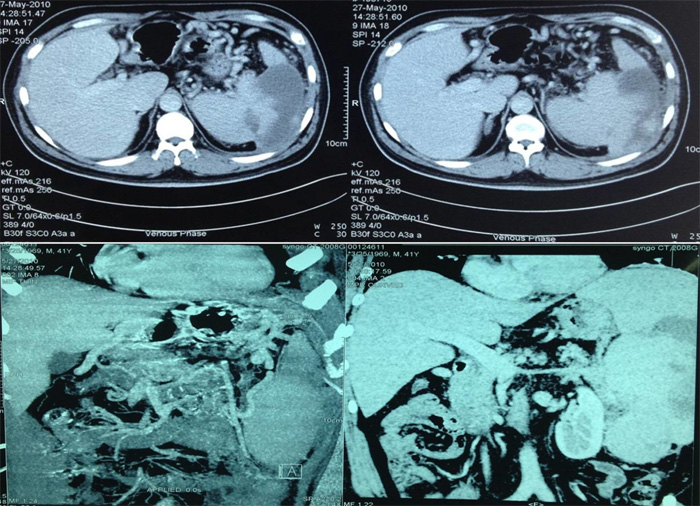

2010年,因“左上腹痛,发热”入我院。腹部CT示:巨脾,脾梗死;脾动脉迂曲,脾静脉纤细,闭塞不除外,脾门、脾周、胃底多发侧支循环形成(图2)。

图2腹部CT检查